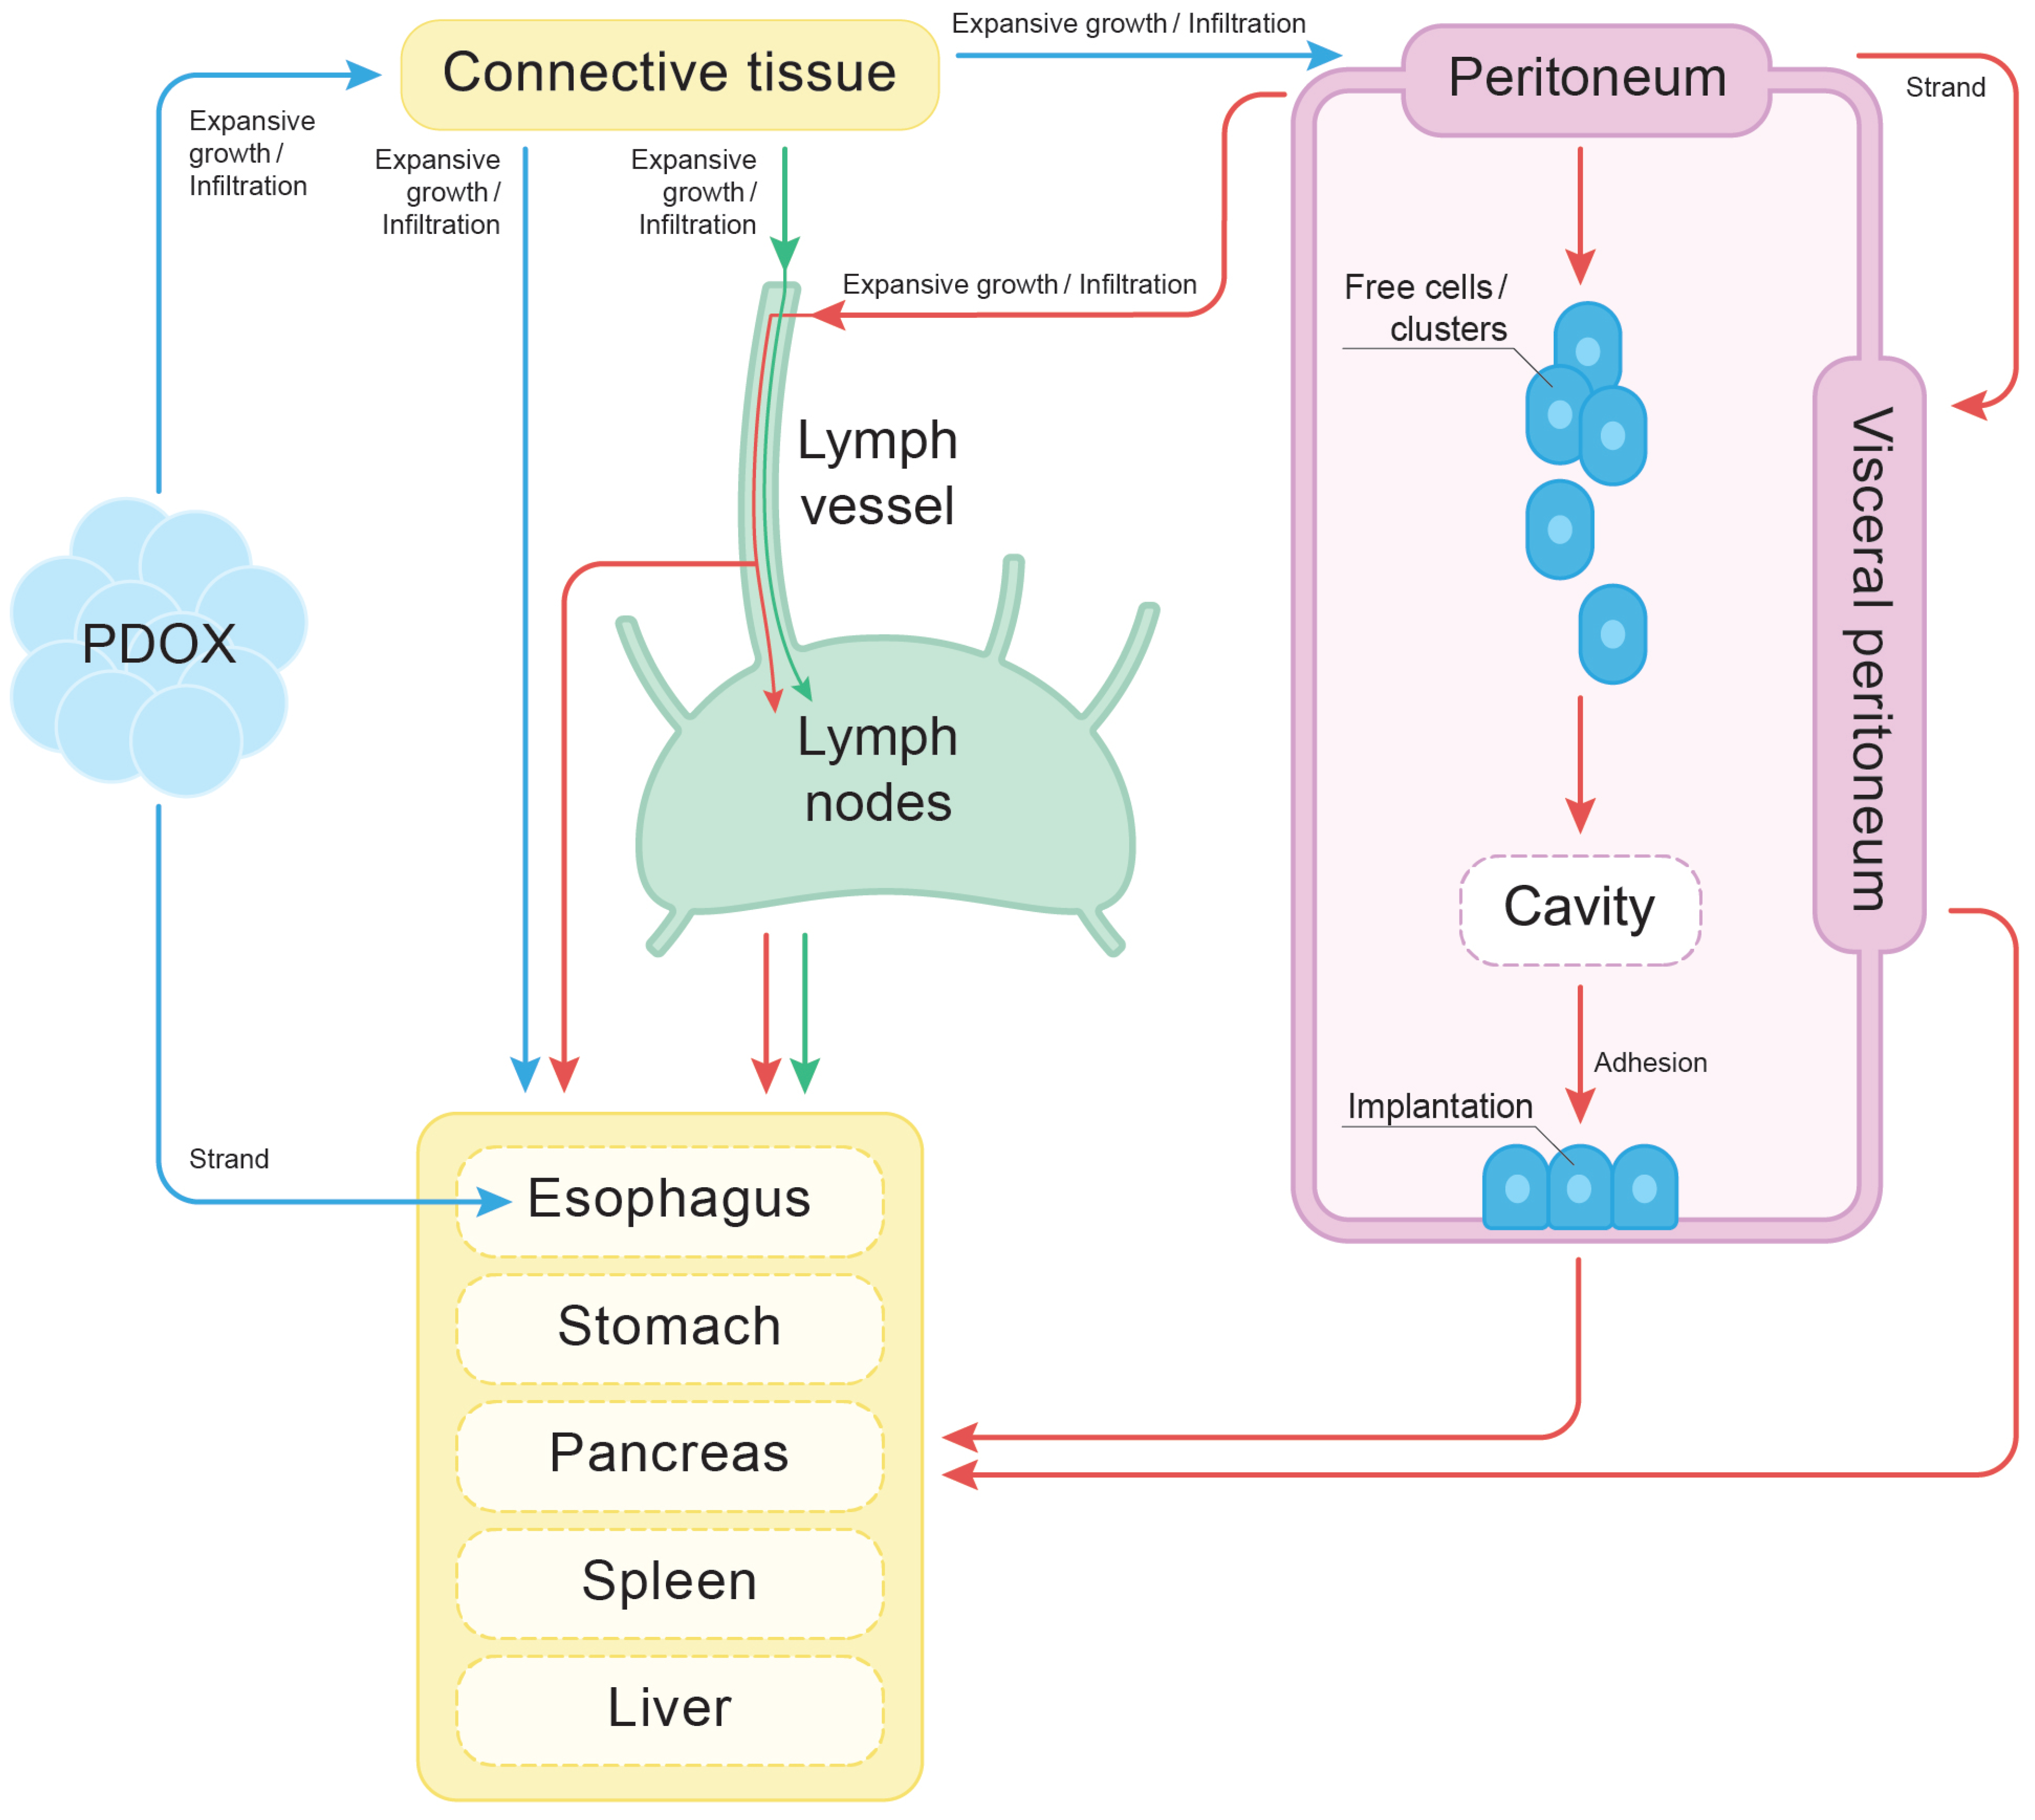

3.6. Peritoneal Dissemination

4.6. The Cyclical Nature of Tumor Dissemination

4.7. The Finger-like Projection Type of Invasion in the Connective Tissue

4.8. Peritoneal Dissemination

6. Conclusions